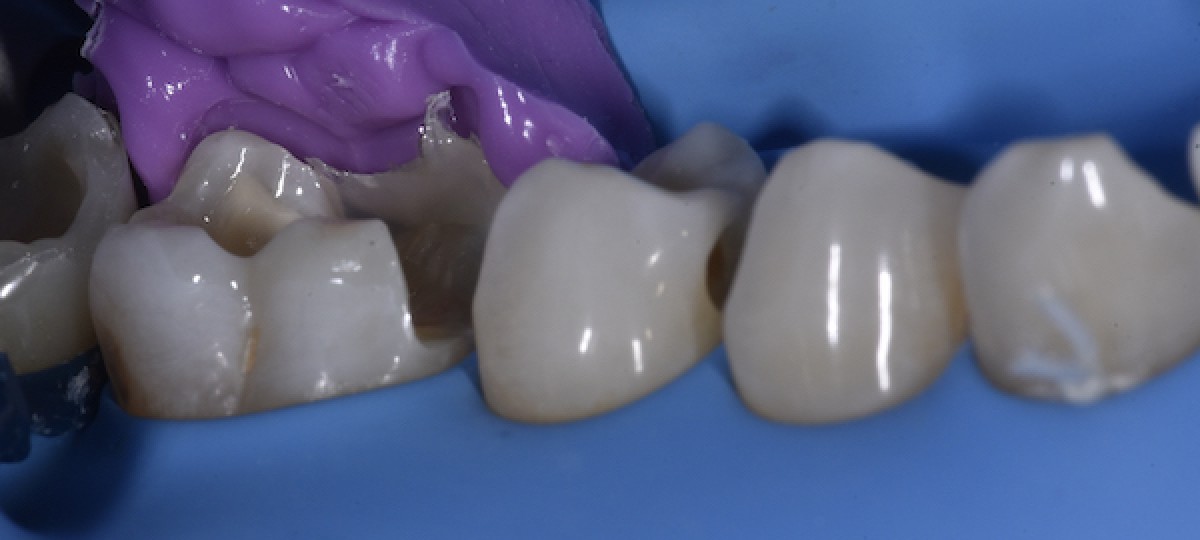

Impression of the lingual cusps of 4.6 with a rigid silicon material (Fig.5)